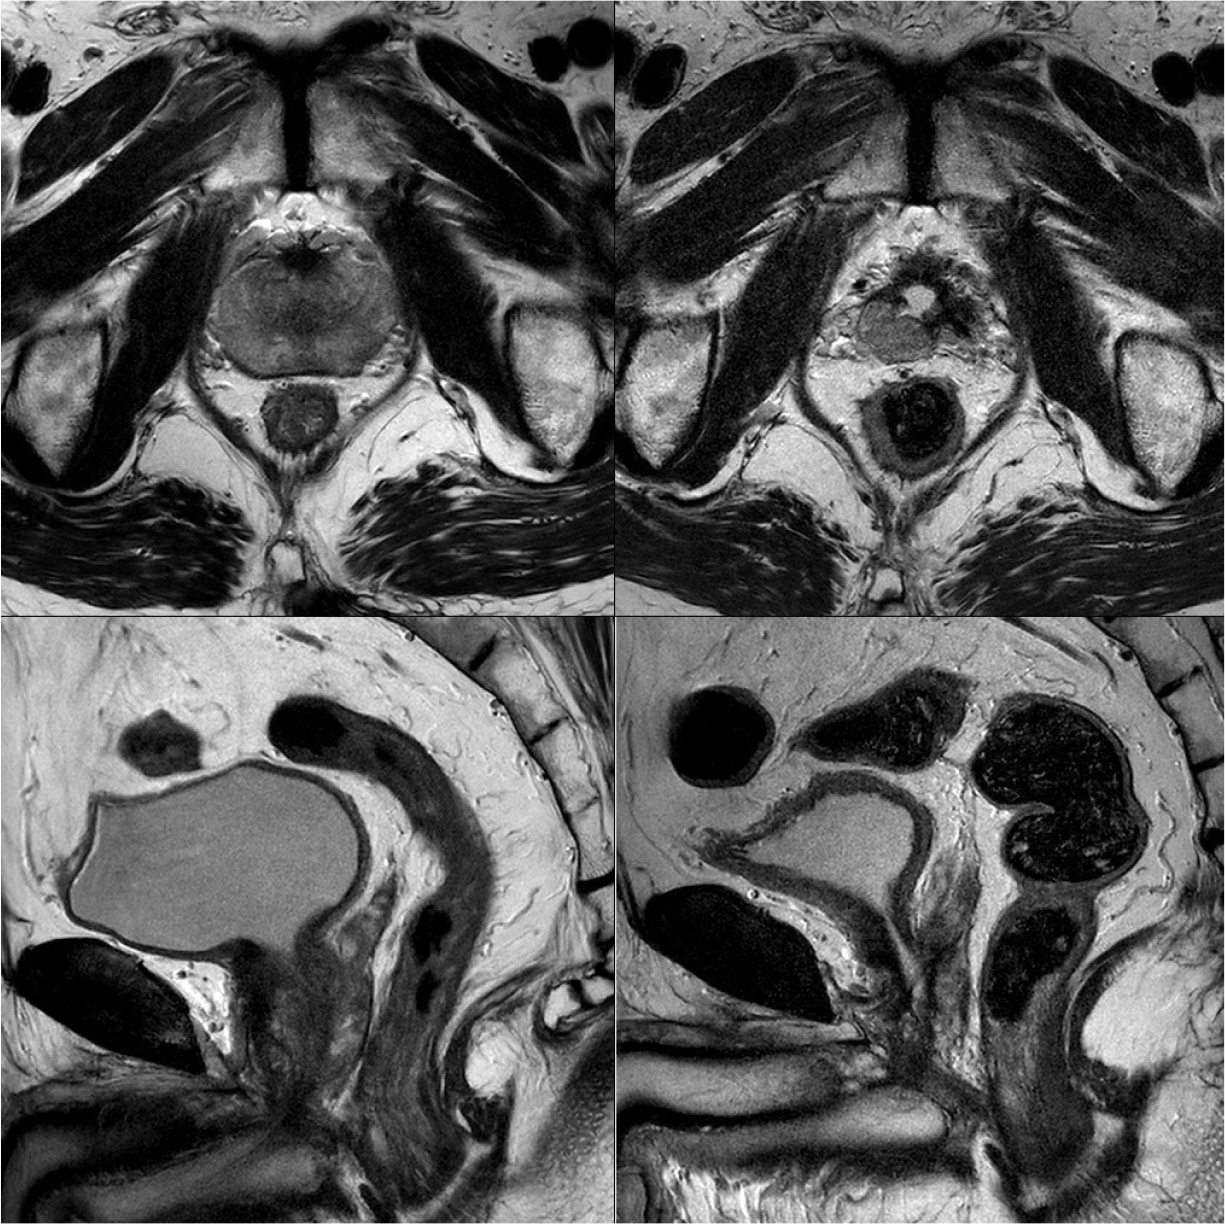

현재의 고강도 초음파 집속술은 Thermal or non-thermal effects 두 개의 효과를 이용한다. 초음파 에너지를 고강도로 집중을 시킴으로 해서 조직 온도를 80도 이상으로 끌어올릴 수 있으며, 이러한 고열은 직접적 조직의 손상을 가져오게 되어 결국 coagulation necrosis에 빠지게 된다. Non-thermal effects는 고강도 초음파 집속술 당시 발생하는 microbubble들이 끌어오르는 진동 현상에 의해서 발생하게 되며, 이러한 mircrobubble은 세포벽의 비가역적인 손상을 초래하게 되어, 세포의 괴사를 초래하게 된다 [그림 1]. 고강도 초음파 집속술은 애초에 초음파를 집중시켜야 하기 때문에, 매우 작은 영역만 한번의 초음파 방출로 태워버릴 수 있다. 기계에 따라서 이 한번에 태울 수 있는 영역의 크기는 다를 수 밖에 없는데, 주로 5 mm에서 1 cm의 크기 정도이다(focal points). 따라서 넓은 면적을 태워버리기 위해서는 고강도 초음파 집속술은 하나의 focal point에 해당하는 영역을 태우고, 프로브를 이동하여 옆에 다시 인접하여 다른 focal point를 태우는 작업을 반복하는 방식으로(focal point라는 점을 나란히 쌓아서) 넓은 면적을 ablation할 수 있게 된다. 현재 출시되어 있는 모든 기계는 이러한 작동 원리를 가지고 있으며, focal point 사이의 남거나 치료 되지 않고 넘어가는 공간이 없도록 focal point마다 약간의 중첩되는 영역을 설정하여 세팅되는 것으로 알려져 있다. 그러나 고강도 초음파 집속술 도중에는 프로브가 계속 회전하고 위아래로 움직이게 되고, 또한 직장의 연동 운동이 존재하기 때문에 전립선은 따라서 같이 움직이게 된다. 이러한 움직임은 focal point와 focal point 사이의 혹시라도 ablation이 되지 않은 skipped lesion의 위험성을 가져오게 되고, 해당 가능성은 술 후의 재발 또는 잔존암으로 이어질 수 있는 위험성이 있다 [그림 2]. 또한 현재 초음파 기반의 고강도 초음파 집속술 기기들은 조직의 온도를 정확하게 측정하는 방법이 없으며, 따라서 원하는 정도의 ablation이 실제 이루어졌는지 술 중에 feedback을 받을 수 있는 방법이 없다. 최근 개발되고 있는 MRI-guided HIFU machine들은 thermometry software들이 내장되어 있어 좀더 정확한 치료가 가능하도록 발전되고 있는 양상이다.